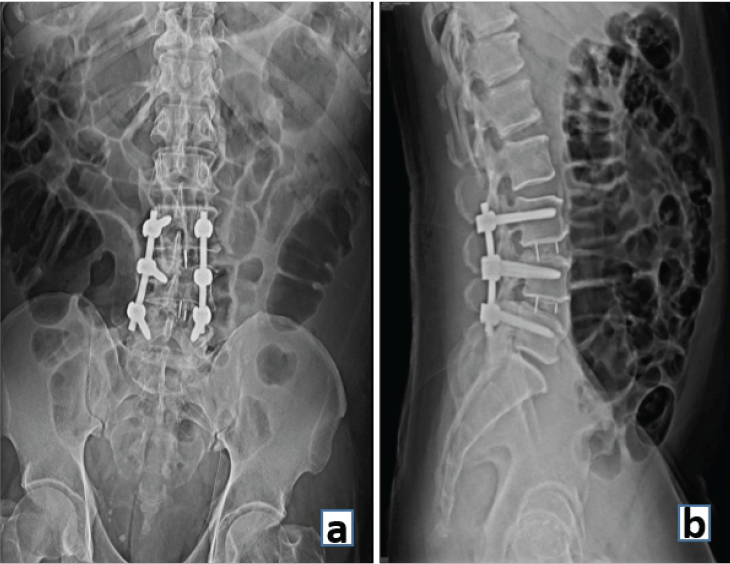

Instrumented fusion

In the spine surgery of today, instrumented fusion involves fusion supported by pedicle screws and rods. The instrumentation provides short-term stability (months) to the spine until long-term stability is achieved by bony fusion of the spinal segments. It is an ongoing race between implant failure and bony fusion as to which comes first! (Fig. 9).

Interbody fusion uses a structural graft such as an allograft, autograft, or a metallic cage in the intervertebral disc space to stabilize an unstable spinal motion segment and promote fusion. FDA-approved intervertebral fusion cages in 1996, which led to a rapid growth in fusion rates for all spinal fusion procedures [13] (Fig. 10).

Figure 10: (a) Anteroposterior and (b) Lateral radiograph demonstrating interbody fusion at L3-4 and L4-5 levels and stabilization with posterior pedicle screws and rods.